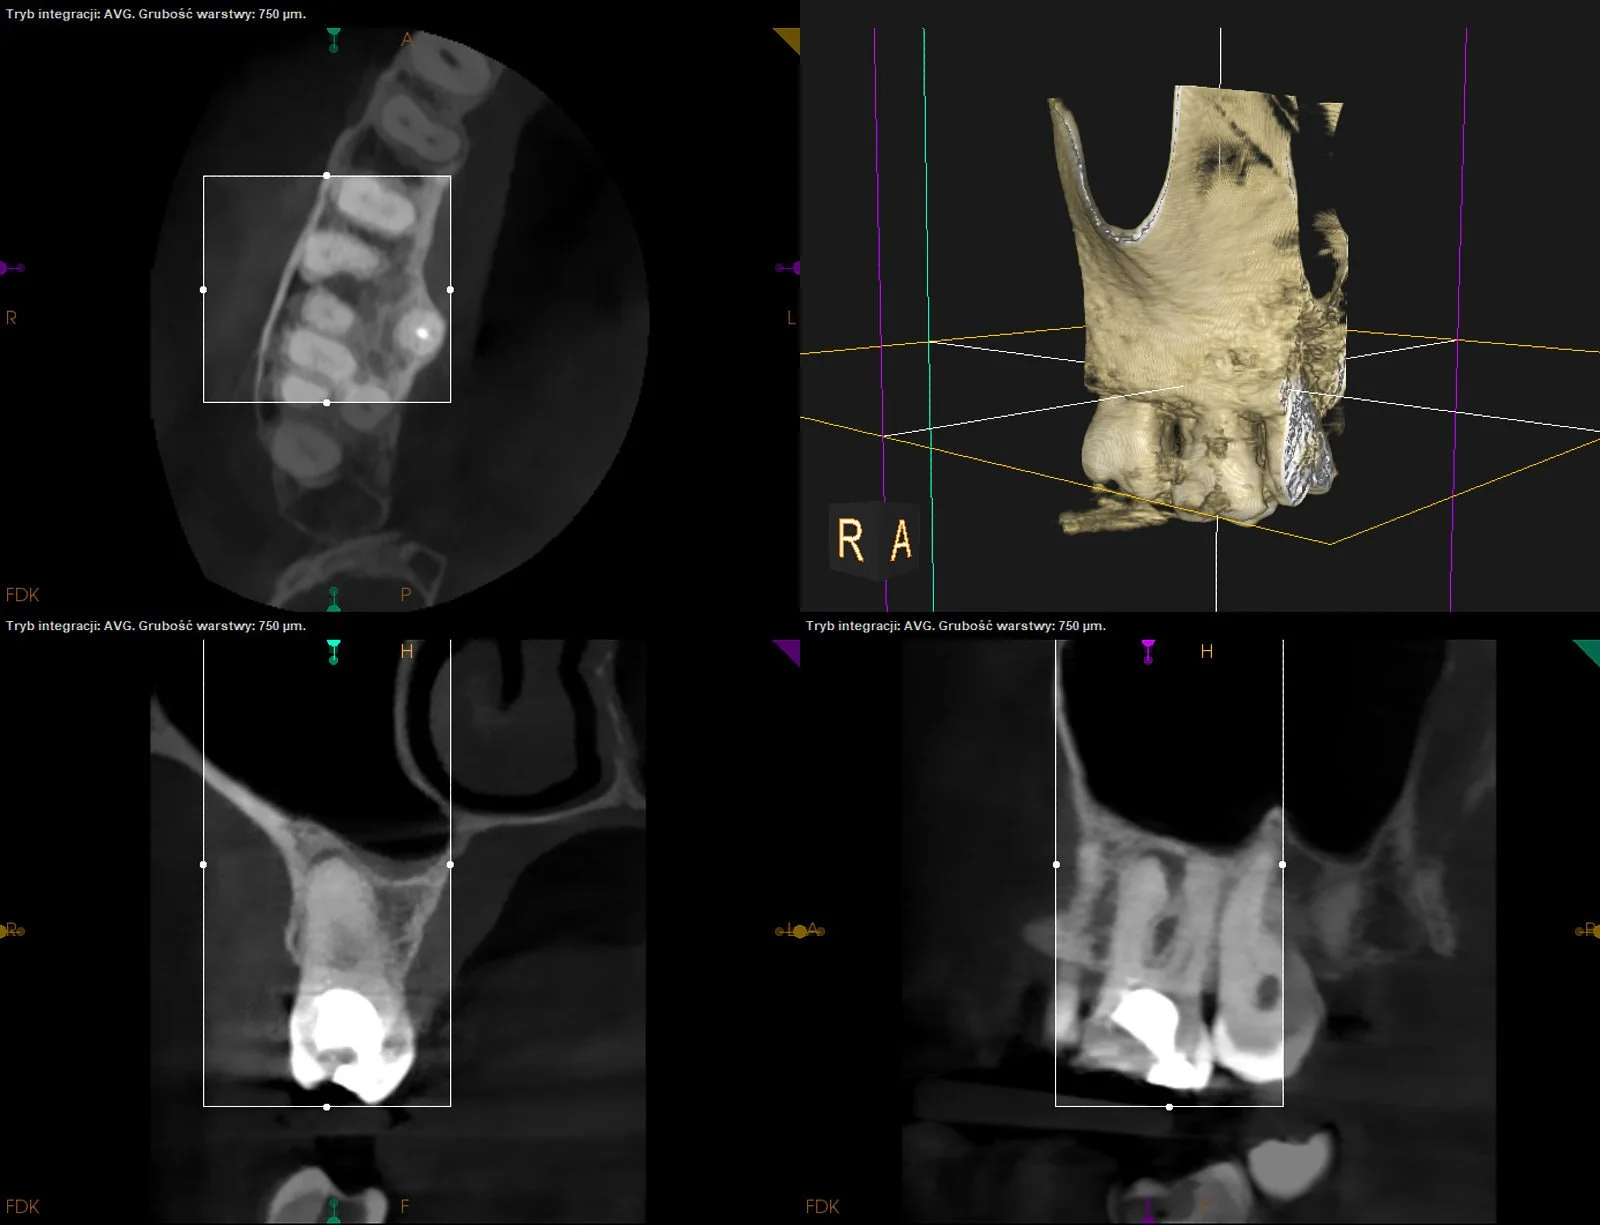

Leczenie kanałowe d.36 z resorpcją wewnętrzną w kanale mezjalnym.